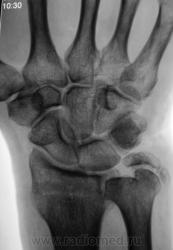

Пациент направлен на рентгенографию лучезапястного сустава.

Пациент направлен на рентгенографию лучезапястного сустава хирургом, была травма. После производства снимков стали допытываться у пациента, о "факте более ранней травмы". Все бесполезно - не помнит, не знает ....

Ваше мнение, уважаемые коллеги?